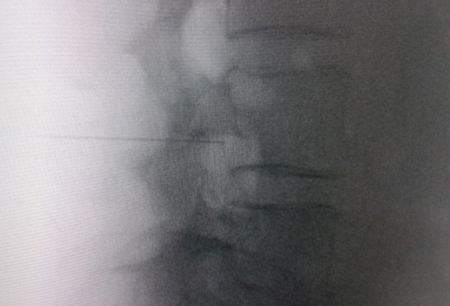

Figura 1

Figura 2